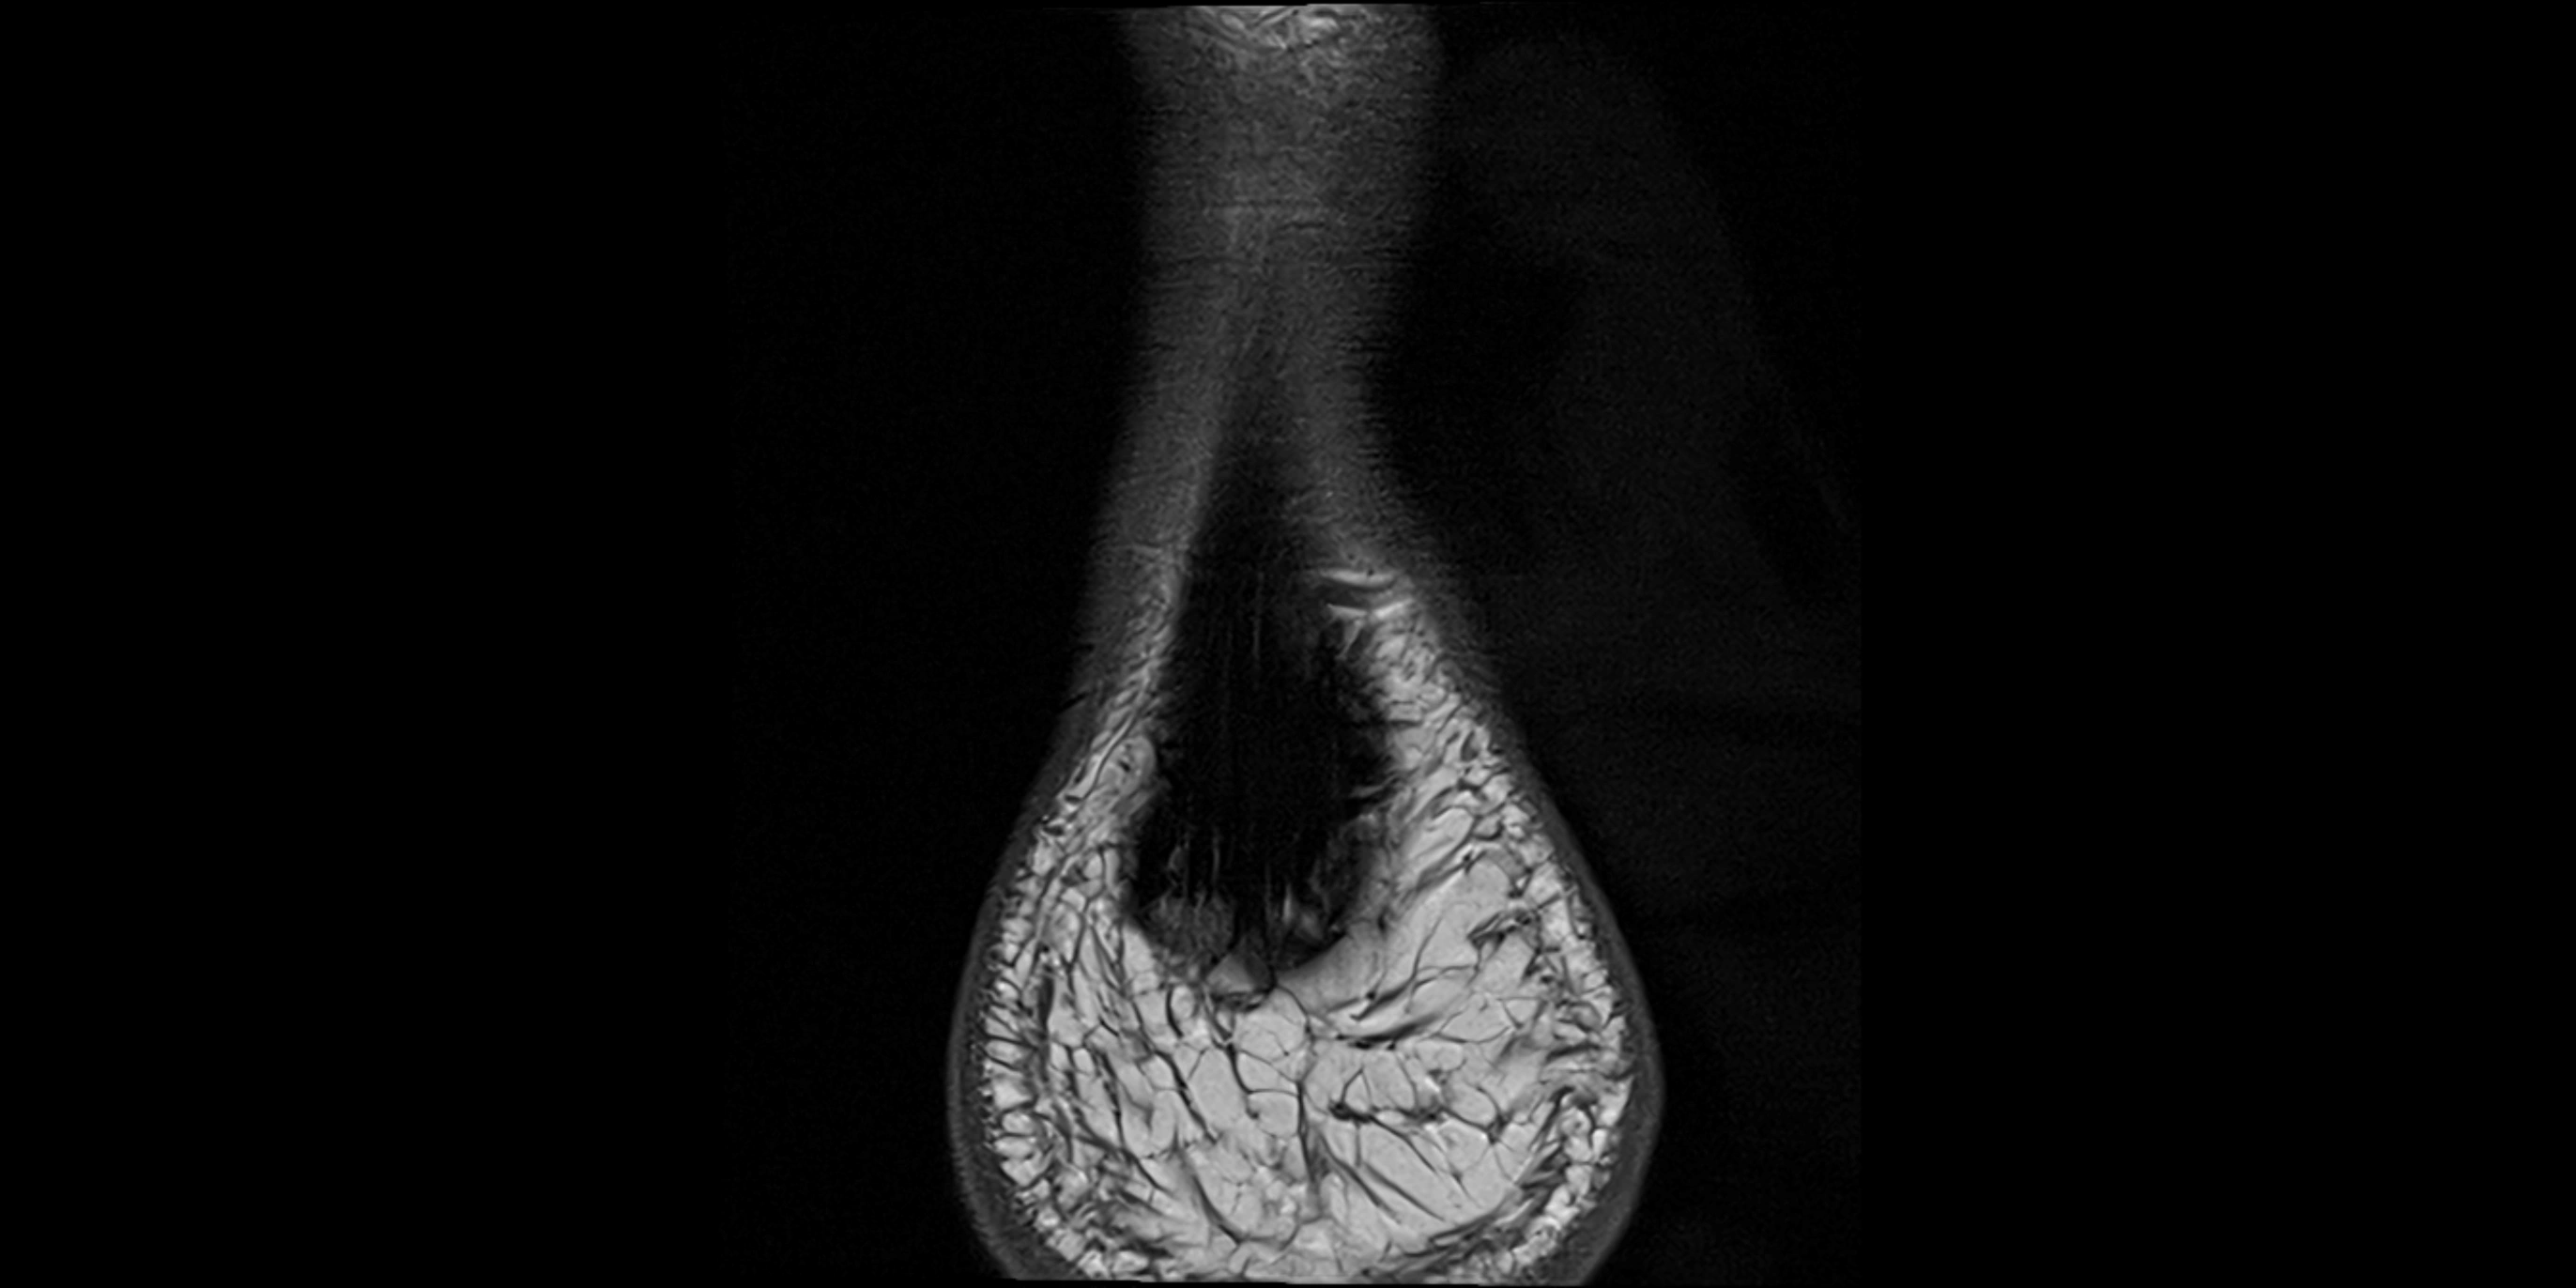

MRI image

image

• STIR:

• Normal muscle: intermediate-to-dark signal intensity

• Normal tendon: very low (dark) signal

• Pathologic tendon: bright hyperintense signal due to edema, strain, or peritendinous inflammation

• Useful for detecting subtle muscle edema or partial detachment at calcaneal origin

• Proton Density Fat-Saturated (PD FS):

• Normal muscle: intermediate-to-dark homogeneous signal

• Normal tendon: low (dark) signal with sharp margins

• Pathology: bright hyperintense areas in the tendon or surrounding soft tissue indicating tendinopathy, tear, or fluid accumulation